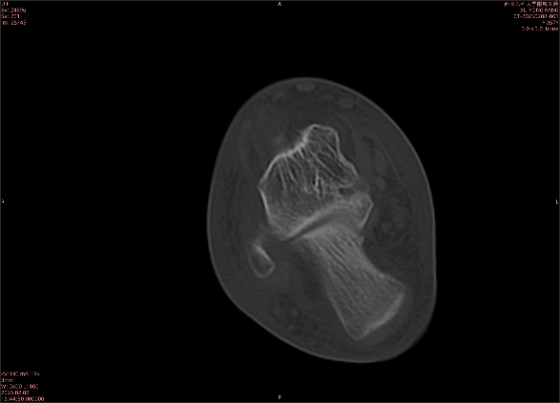

舉例圖像

圖1

專業(yè)解釋看不懂沒關(guān)系,大家看圖1和圖2就可以了,這是同一個患者跟骨的磁共振和CT圖像,圖1的紅色箭頭指示的黑線就是磁共振圖像顯示的骨折線,一目了然。而對比圖2的CT圖像上并未顯示異常。

這下大家明白了吧,如果懷疑隱匿性骨折優(yōu)先選擇磁共振檢查